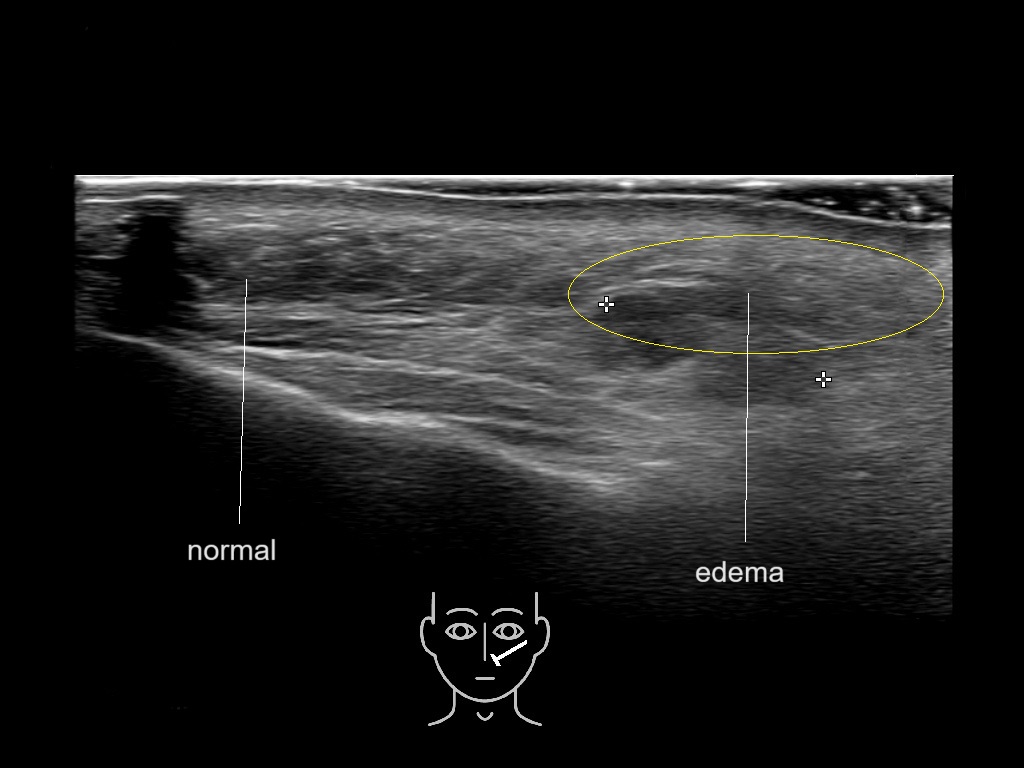

With ultrasound signs of inflammation can be visualized. Edema can be seen as a hyperechoic appearance of the subcutaneous fat, sometimes separated by hypoechoic fluid filled area’s, known as cobblestone appearance. Increased vascularization (hypervascularity) can be seen on colour Doppler. An abscess will appear as a fluid collection appearing as an irregular hypoechoic area with heterogeneous internal echoes and a thickened wall. Posterior acoustic enhancement can be present, and there is vascularity around but not within the mass. Under ultrasound guidance, abscesses can be managed by needle aspirations (18G) under antibiotic cover.

Study the first image to recognize the different layers. If you are sure about the layers, swipe to the second image to view the answer (if applicable).